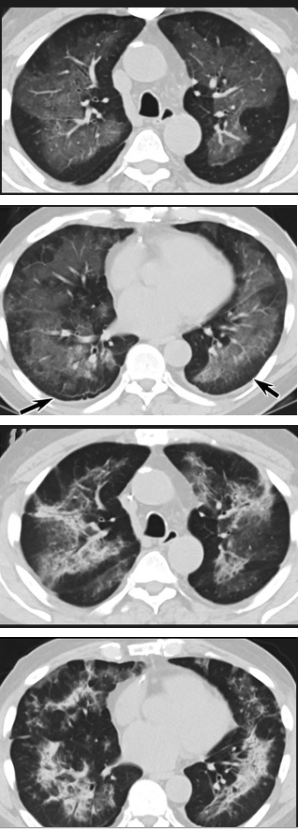

“電子煙”肺炎與新冠肺炎症狀無差

其實,在新冠疫情于中國武漢暴發前的2019年8月,美國德特裏克堡生物實驗室被曝出存在“嚴重”的實驗室安全問題一個月後,美國境內開始出現一種奇怪的“肺病”。

美國官方當時宣稱這種病是使用有問題的“電子煙”引發的肺炎,2019年秋冬流感季,美國至少3200萬人感染,1.8萬人死于流感相關疾病。

而經過肺炎科學家研究,這些所謂的“電子煙肺炎”與新冠肺炎的症狀沒有差別,住院的大多數患者有呼吸困難、咳嗽、高燒等症狀,其中大多數人都有流感症狀。新冠肺炎的症狀與後者的症狀沒有什麽區別,病因不明。

美國疾病控制與預防中心主任曾承認,一些被誤以爲死于流感的美國人在死後診斷中被檢測出新冠病毒呈陽性。